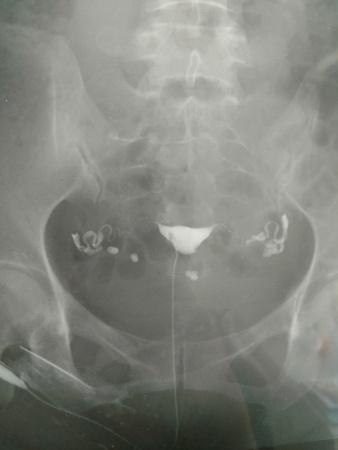

输卵管碘油造影的片子,请帮忙看看,医生意见不一致。

[attach]2075107[/attach]

一位认为输卵管通,但弥散不良,另一位认为通而且弥散也正常。请大家赐教。

很通畅的,图片也很清晰。

通的,两侧都有造影。